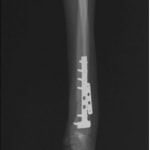

トイプードル 右遠位橈尺骨短斜骨折のALPSによる内固定

Locking Compression Plate

LCPは、スクリュー(ネジ)とプレート(金属の板)をロックする特殊な構造により骨折部位を固定する新しい世代のプレートシステムです。ひとつのホールでロッキングスクリューとスタンダードスクリューの使用を選択できるユニークな構造をしているため、骨折断端間の圧迫を目的とした従来型プレート固定法に加え、高い角度安定性を有するロッキングスクリューを用いた固定法の選択が可能です。従来のプレートシステムでは困難だった部分の骨折や癒合不全の症例に高い治療効果をもたらします。

当院ではAdvanced Locking plate system(ALPS)と、Locking compression plate system(LCPS)という骨接合法で骨折症例の治療を行っています。